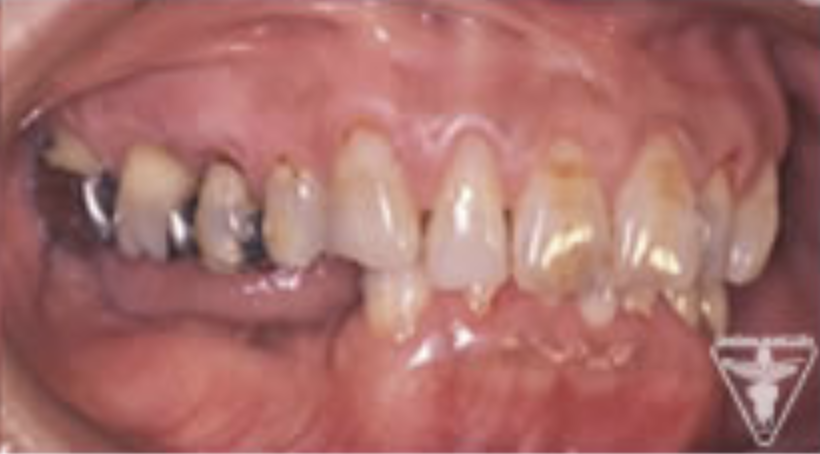

治療後の経過状態

- 術後10年経過し、維持的リコールを守られ、歯周の炎症、歯肉ポケットの管理

- 噛む力のコントロールにより、変化のない口腔内を維持していく